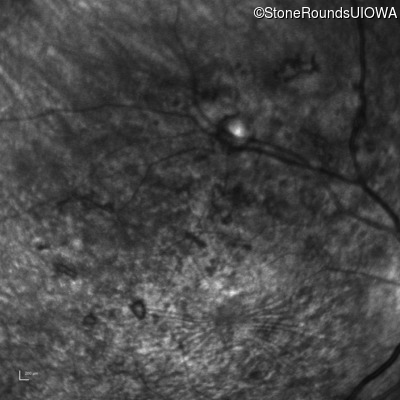

Infrared Fundus Photograph - Right - Count Fingers 3'

Exemplar